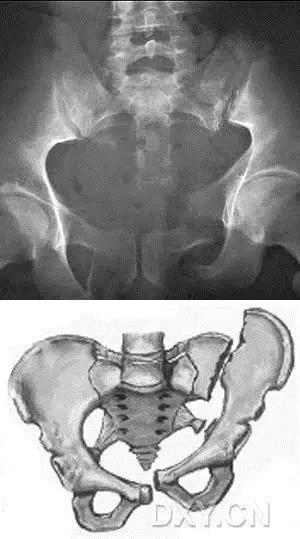

2. Malgaigne 骨折 (bucket handle 骨折,即桶柄骨折)

不稳定性骨盆骨折伴有前方和后方的骨折线累及髋关节。

(来源:radiopaedia)

3. Straddle 骨折

双侧耻骨上下支骨折。

(来源:learning radiology)